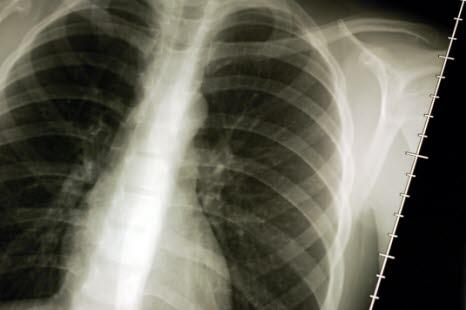

Typiske plager er tungpusthet og hoste. Når dette opptrer like etter eller under en lungebetennelse, eller i forbindelse med operasjoner, vil man ofte få mistanke om tilstanden. Men sikker diagnose stilles først ved røntgenundersøkelse av lungene.

Ved røntgen av lunger er de typiske forandringene at atelektasen viser seg som en liten kileformet ensartet skygge på røntgenbildet